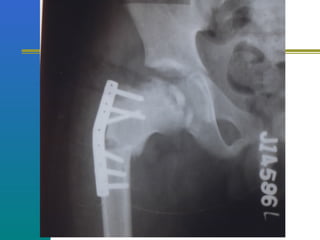

Surgical treatment is the

standard

Surgical options

Insitu pinning

Reduction and fixation

Corrective osteotomies

Insitu pinning

Image intensifier control

Cannulated screw fixation

Surgical treatment

Contain head by osteotomies

Femoral or acetabular

Varus derotation osteotomy of

femur commonly done

VARUS DEROTATION

OSTEOTOMY

 Redistributes the

load on the femoral

head more

uniformly

 Relaxes the

muscles by

increasing the

functional length

of the femoral neck

 Enhances the

reciprocal

moulding of the

head-

BIOLOGICAL

PLASTICITY

 Improves blood

supply & healing